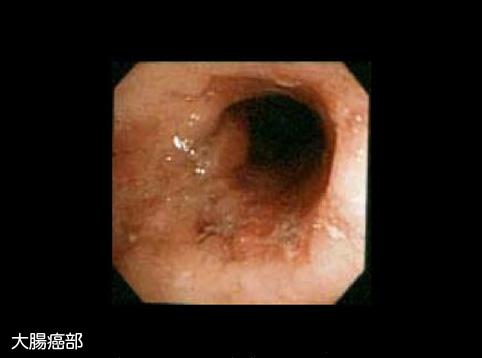

症例提示(所在地,施設名等): 北海道・ JA北海道厚生連 札幌厚生病院 (今村哲理先生からの提供症例)

疾患(病理主体)の分類炎症性・潰瘍性疾患/潰瘍性大腸炎

部位(臓器別)大腸/下行

検査方法内視鏡

腫瘍の肉眼分類4型(びまん浸潤型)/

病変の最大径(ミリ)40以上

腫瘍の深達度ss(a1)